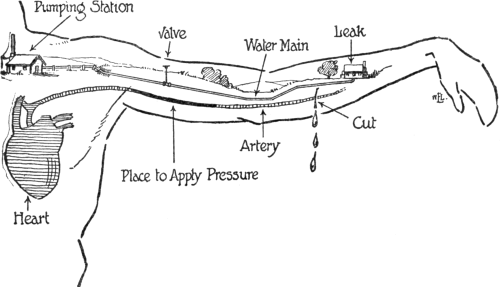

FIRST AID TO THE SICK AND INJURED—Object

1478–1522 |